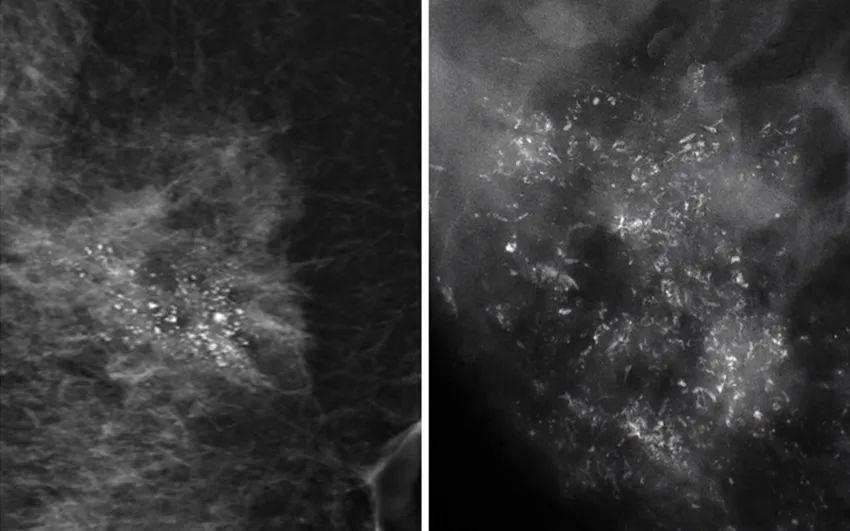

因此,惡性鈣化點(diǎn)的特點(diǎn)是:聚集很緊密,簇聚于局部區(qū)塊,且鈣化點(diǎn)很小,形狀不規(guī)則,每個(gè)點(diǎn)都不太一樣,或有針尖狀、小桿狀、分叉狀、簇狀及泥沙樣多屬于惡性病變。

每一個(gè)檢查設(shè)備都有各自擅長的地方,由于乳腺鉬靶是把乳房夾起來照X線,鈣質(zhì)可以吸收較多的X線,因此其主要優(yōu)勢在于對微小鈣化檢出敏感,可以降低乳腺癌患者的死亡率,是歐美國家乳腺癌篩查優(yōu)選的影像檢查。但相對比超聲檢查,局限性在于對致密型乳腺敏感度低。

高頻超聲能夠提供高分辨率的二維圖像,能清晰顯示乳腺內(nèi)局灶性病變,并可觀察局灶性病變內(nèi)部及周邊血流分布、走行形態(tài)及血流動力學(xué)信息,但對微鈣化病灶的檢出率略低于乳腺鉬靶檢查,檢出率約為79%。

隨著超聲醫(yī)學(xué)的發(fā)展,超聲的分辨力也越來越高,對乳腺微鈣化應(yīng)有較高的顯示率,常規(guī)超聲對微鈣化乳腺癌的診斷價(jià)值已與乳腺鉬靶相仿。但超聲檢查和鉬靶檢查各有優(yōu)勢,各自仍都是不能被取代的。